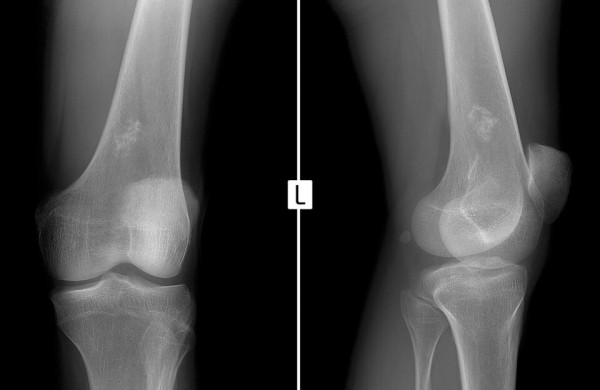

Анализы и проведенная компьютерная томография помогли установить  конечный диагноз — у малышки саркома Юинга с многочисленными метастазами в легких. Ей уже сделана одна операция, в ходе которой была взят дополнительный анализ на биопсию.